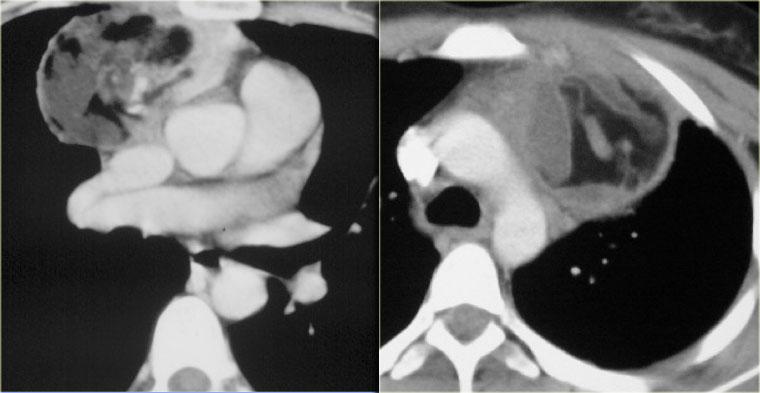

Các hình ảnh cho thấy u tuyến ức ở bên trái và ung thư biểu mô ở bên phải.

Ung thư biểu mô tuyến ức đã xâm lấn tĩnh mạch chủ trên (mũi tên).